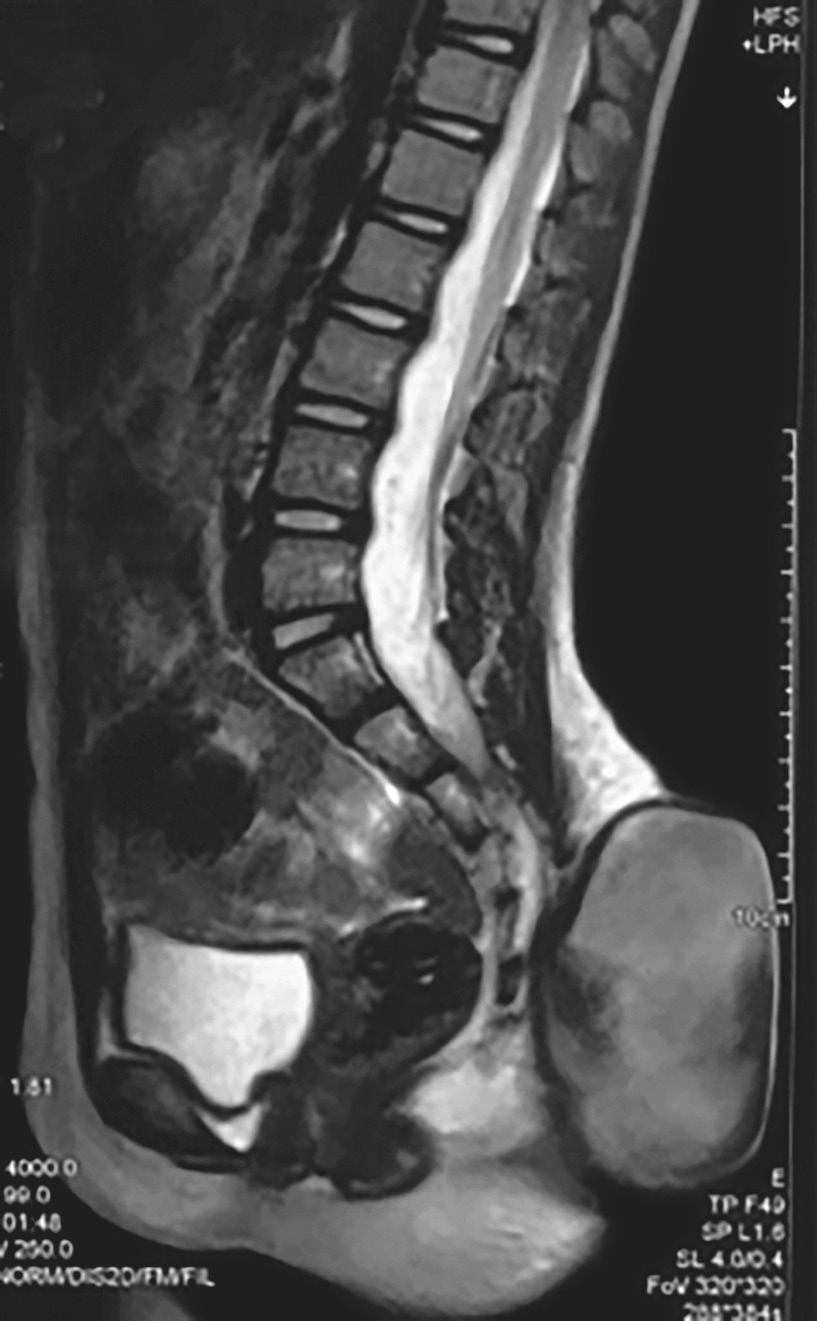

辅助检查:MRI(图4-1-6)示脊柱裂伴脊膜膨出、脊髓栓系低位。CT(图4-1-7)示S 1 、S 3 ~S 5 骶椎裂,伴骶尾部脊膜膨出;脊髓栓系低位可能。

图4-1-6 MRI图像

治疗过程:患儿出生后即发现腰骶部肿物,初时较小,未予特殊处理。目前包块逐渐增大至约10cm×8cm,表面无毛发生长,质软,囊性,按压肿物大小无变化。腰骶CT三维重建示:S 1 、S 3 ~S 5 骶椎裂。腰骶MRI示:①脊柱裂伴脊膜膨出;②脊髓栓系低位。结合病史及症状体征和影像学检查,诊断为:脊柱裂伴脊膜膨出,脊髓栓系。

现病史:患儿半年前开始逐渐出现跛行,逐渐加重,伴便秘,大便每3~4日1次。小便有力,无漏尿、失禁等。就诊于医院神经外科门诊,行MRI(图4-1-8)提示脊髓栓系,收入院。

图4-1-8 患者MRI图像

辅助检查:MRI提示骶椎裂,圆锥位于L 3 水平。